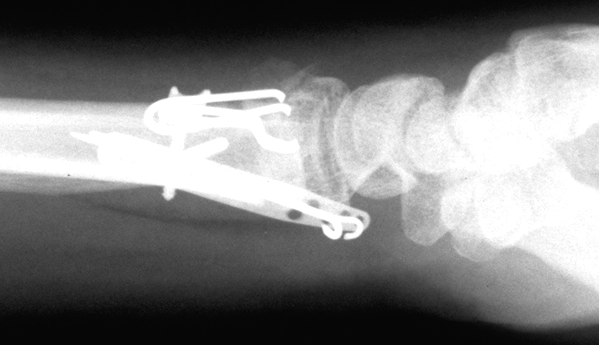

Case 2 Postop